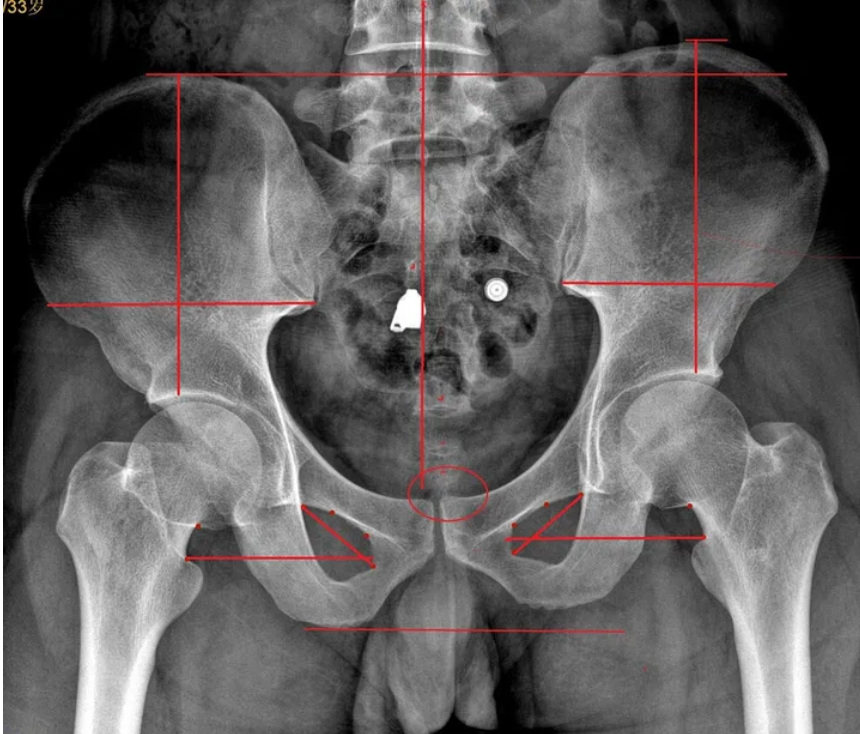

⑧X线检查:脊柱侧弯,骶髂间隙增宽,两侧髋骨不等宽,髂嵴不等高,闭孔不对称。

⑥骨盆两侧骨性结构不对称:两侧髂前、髂后上棘、髂嵴高度不一致;

⑤双下肢不等长,短腿侧足异常旋前;